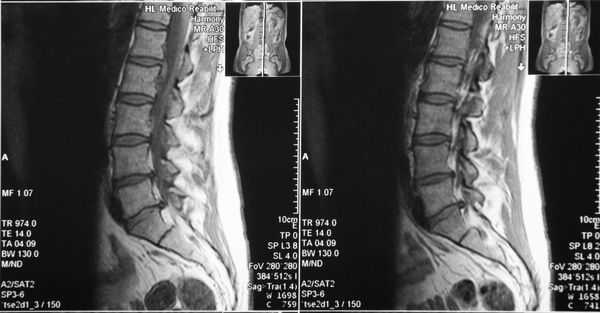

Определение болезни. Причины заболевания

Стеноз позвоночного канала — это состояние, когда размеры позвоночного канала на поперечном срезе уменьшаются, либо уменьшаются размеры межпозвонковых отверстий, в результате чего сдавливается содержимое канала (спинной мозг, корешки) . Как правило, стеноз позвоночного канала выявляется на уровне нижних поясничных позвонков, реже — в шейном и грудном отделах позвоночника.

Позвоночный (спинномозговой) канал — это пространство внутри позвоночного столба, которое спереди образуют тела позвонков и межпозвонковые диски, с боков и сзади — дуги позвонков, соединенные желтой связкой. На поперечном срезе он треугольной или овальной формы. [1]

У многих людей без врожденных нарушений развития позвоночника встречается конституционально анатомически более узкий позвоночный канал, чем в среднем. Нормальная глубина позвоночного канала в поясничном отделе составляет 13-25 мм, в шейном — 15-20 мм.

Центральный стеноз — уменьшение переднезаднего размера позвоночного канала.

- относительный стеноз — переднезадний размер составляет менее 12 мм.

- абсолютный — менее 10 мм.

Латеральный стеноз — уменьшение размеров межпозвонкового отверстия до 4 мм и менее.

Если уменьшаются все размеры позвоночного канала, это комбинированный стеноз.